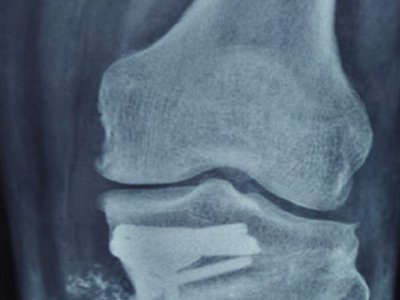

Deformed knees in younger and middle aged patients alongside pain can be displeasing. Since replacing the knees is not an option in these patients Dr. Nikhil Sharma is experienced in keeping the natural/native knee intact and reshaping the knees to help patients recover.